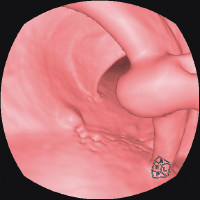

Colonic polyp